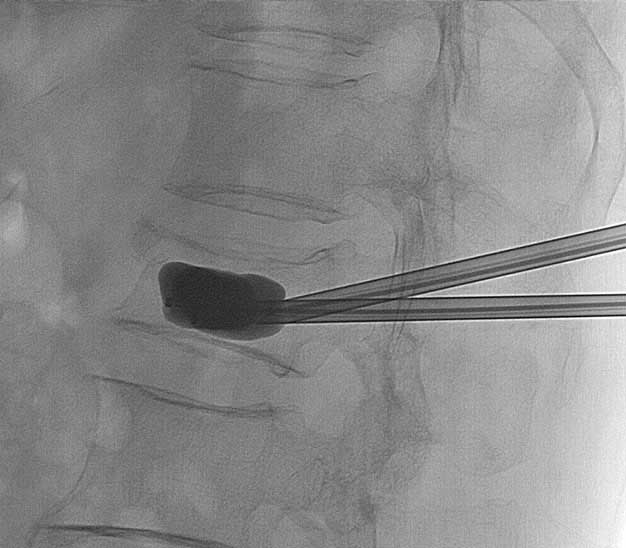

Caso haja persistência da dor, sinais de instabilidade da fratura e/ou sintomas neurológicos associados, o tratamento cirúrgico pode ser indicado. Atualmente existem procedimentos minimamente invasivos como a cifoplastia (injeção percutânea de cimento na fratura) e até procedimentos de descompressão e fixação aberta. Cada caso tem uma indicação específica e deve ser direcionado pelo médico especialista.

Alguns tipos de fraturas podem ter indicação cirúrgica devido a instabilidade local ou até acometimento neurológico associado. Nesses casos, procedimentos minimamente invasivos como a cifoplastia (injeção de cimento) podem ser necessários. Casos mais graves com grande instabilidade/lesão neurológica ou fraturas múltiplas, podem requerer cirurgia aberta de artrodese.